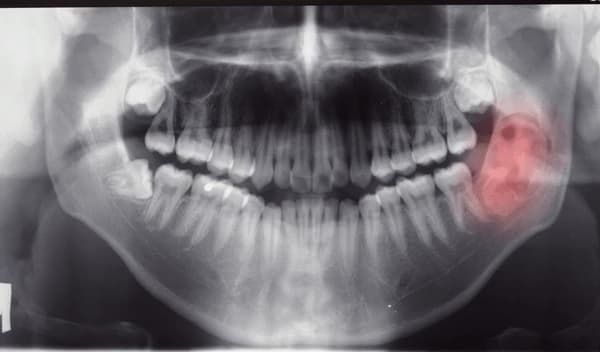

الأكياس السنية

الأكياس السنية: الأسباب والأعراض والتشخيص والعلاج